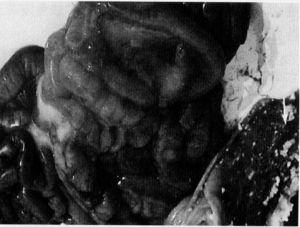

豬血凝性腦脊髓炎 病豬腦部病變尚無有效的防治藥品和預防疫苗,主要依靠加強綜合性防治措施,注重加強口岸檢疫,防止引入病豬。一旦發生該病,要及時診斷,嚴格隔離消毒,防止疫情蔓延擴散,以免造成重大經濟損失。多數流行地區處於呼吸道亞臨床感染狀態。母豬多在初產前即感染病毒,通過初乳抗體可以有效地保護仔豬,仔豬受到感染時也處於亞臨床狀態。在新建豬場,母豬產前未感染PEV時,3周齡以內的仔豬可能出現臨診症狀。所以,維持母豬的感染狀態可以避免仔豬發病。仔豬一旦發生本病,很難自然康復。應及早診斷,防止本病蔓延擴大。2~3周后出生的仔豬可通過母源抗體獲得保護。在此之前未獲得母源抗體的仔豬,可在初生後注射高免血清建立被動免疫。